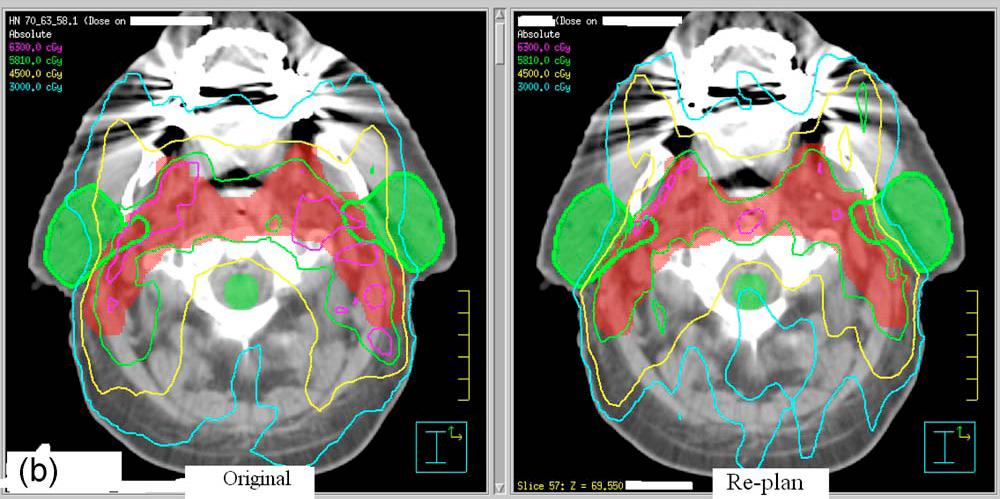

- A

Statistical Approach for Achievable Dose Querying in IMRT Planning

-

- P. Simari, B. Wu,

R. Jacques, A. King, T. McNutt, R. Taylor, and M. Kazhdan

- Medical Image

Computing and Computer Assisted Intervention (MICCAI) (September

2010)

Abstract:

The task of IMRT planning, particularly in head-and-neck cancer, is a

difficult one, often requiring days of work from a trained dosimetrist.

One of the main challenges is the prescription of achievable target

doses that will be used to optimize a treatment plan. This work

explores a data-driven approach in which effort spent on past plans is

used to assist in the planning of new patients. Using a database of

treated patients, we identify the features of patient geometry that are

correlated with received dose and use these to prescribe target dose

levels for new patients. We incorporate our approach in a

quality-control system, identifying patients with organs that received

a dose significantly higher than the one recommended by our method. For

all these patients, we have found that a replan using our predicted

dose results in noticeable sparing of the organ without compromising

dose to other treatment volumes.